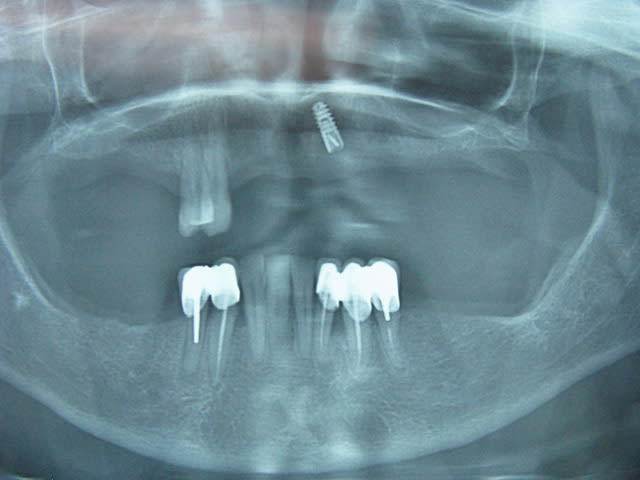

Tu vois , il y a les érections médiatiques ... plus près de mon cabinet un stomato qui pratique les mêmes prix qu'en Bulgarie.

Dernièrement il s'est mis à l'implanto ...avec succès d'ailleurs !

T'imagine pas comme j'ai peur .

Alors comme tu ne comprendras pas la grande stomatologie appliquée à la dentisterie moderne , tu mets un clip sur l'implant , et un stelitte .

Le reste je m'en occupe , mais c'est vrai le plus dur c'est de récupérer les documents ..."je rembourse la somme de 0.03 euro à madame x ..." .